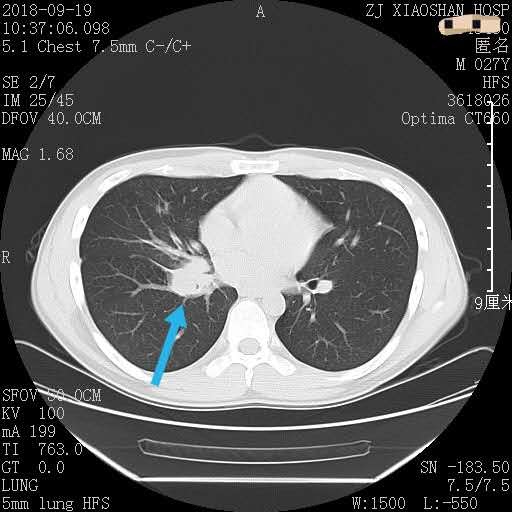

别看患者小吴年纪不大,可却已经是医院的“常客”了,近两年来,他已经门诊就诊78次,甚至连住院,都已经5次了。小吴第一次住院是在2018年9月。到呼吸内科病区住院时,护士们对他的第一印象就是非常“潮”,一枚单身小帅哥。但让护士们头疼的是小吴经常神出鬼没,一个不留神,人就不见了,总是偷偷溜出去抽烟。小吴的病也和吸烟有着千丝万缕的关系。27岁的他是因“咳嗽、咯血伴右胸痛2月余”入院的,入院后查胸部螺旋CT增强扫描提示:右肺中叶支气管开口区、下叶多发底段支气管增厚、狭窄,右下肺门强化肿块。起初医生还以为是特殊病原菌感染,但继续深入检查发现患者的右肺中叶支气管开口及右肺下叶基底段开口均可见新生物,予以活检病理,结果显示为“低分化癌”(表示肿瘤的恶性程度高,预后差),同时查出有骨转移,丧失了手术机会。记得病理切片出来的那天,小吴的父母是笑着来办公室的,可结果犹如晴天霹雳,让这个独生子女家庭瞬间飘摇在风雨中。母亲甚至嚎啕大哭,边哭还边骂:“这个不孝子,让他别抽烟别抽烟,还每天三四包地抽……”呼吸内科副主任陈腊青询问病史后发现,小吴家里没有恶性肿瘤家族史,父母、祖父母(二系三代)也都身体健康,自己也是小白领一个,没有特殊职业暴露史,所以致病主因就是吸烟。幸好,经过基因检测,小吴获得了靶向治疗的机会,一直服药治疗,生存期已达17个月。半年前小吴还出现了脑转移,目前病灶虽然控制稳定,但是他已经丧失了劳动能力,生活质量很差,并且随时可能复发。烟草和癌症据呼吸内科毛洪刚主任介绍,香烟燃烧的过程中可产生数千种有害物质,大致可分为6类:1.醛类物质:这一类物质主要对人体的呼吸道有很强的刺激作用。